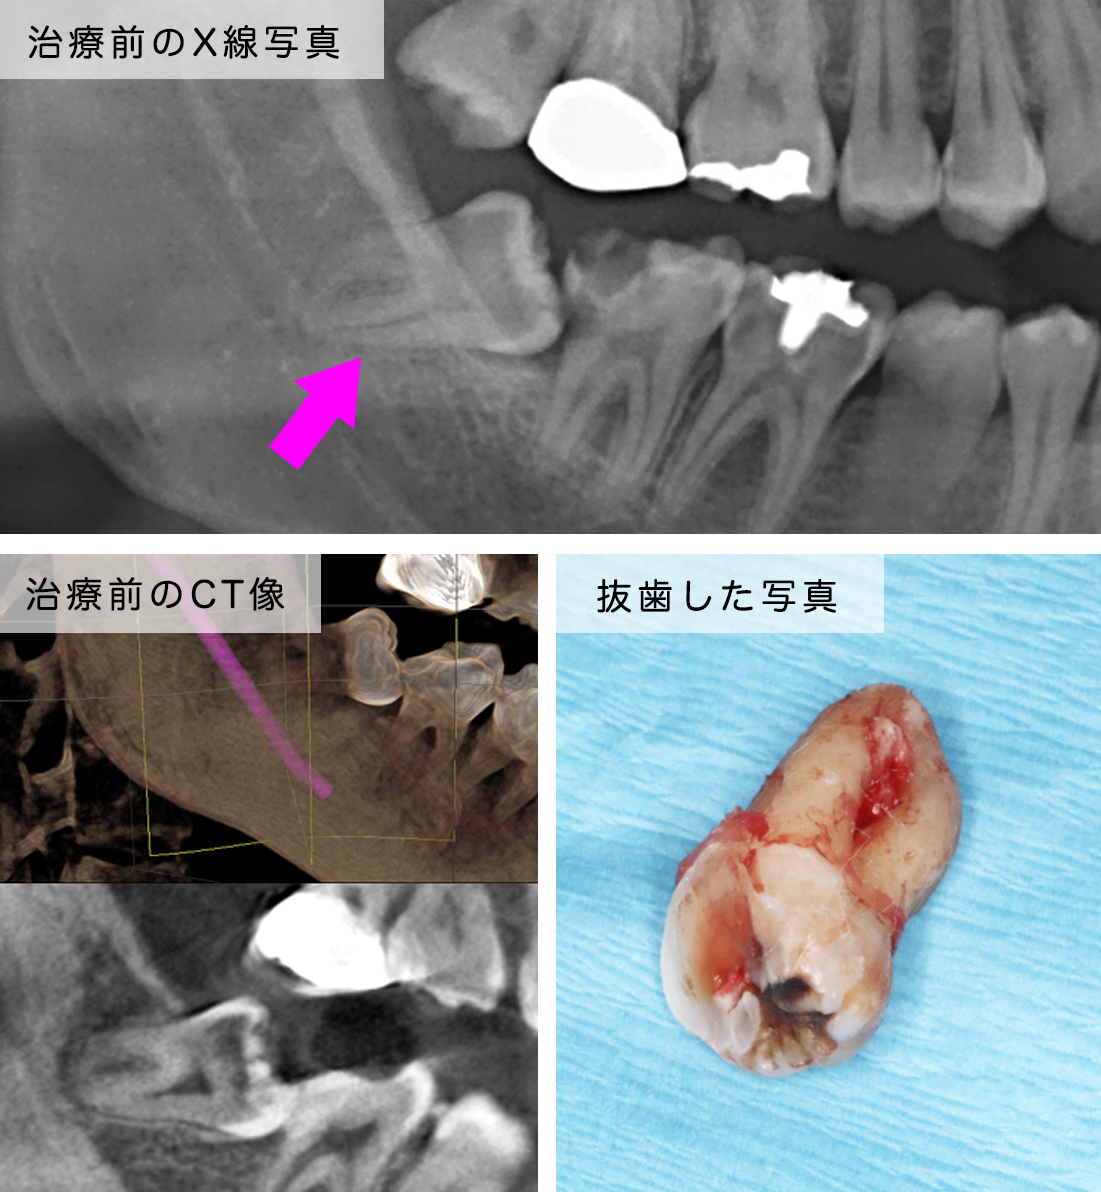

case.5右上の歯茎が腫れて痛い

治療の説明

右上の親知らずが原因で隣の歯の歯周ポケットが深くなっているところがありました。なので抜歯を行い1週間後に抜糸をして治療を終えました。

主訴右上の歯茎が腫れて痛い

治療期間1週間

治療費5,000

治療のリスク

• 2、3日は腫れる事があります

(上顎は殆どのケース腫れません)

• 上顎洞と交通する可能性があります

(この方は交通しておりません)